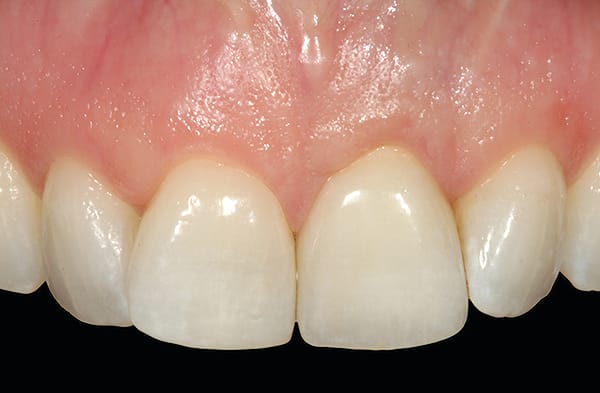

A young woman presented with a midfacial recession defect of roughly 4 mm to the junction of the abutment-implant interface (Figure 1) that was also present in her smile (Figure 2). She had previously consulted several surgeons who were hesitant to treat her because of the defect and high smile line. A cosmetic dentist subsequently referred her to the authors.

Before a clinician can decide on treatment, a diagnosis must be made whether the implant is healthy or not, meaning normal bone levels around the implant. Another decision of concern was whether to retain the dental implant. It was determined that the implant was healthy, however the recession defect was due to an overcontoured custom abutment secondary to excessive facial implant angulation (Figure 3). The tendency for most surgeons when presented with such a recession defect is to think of a “root” coverage type surgical procedure. Patients with a thin or intermediate phenotype may not respond well to such a technique. It was also mentioned previously that an exposed implant abutment is absent of blood supply and may be contaminated with endotoxins that would constrain the predictability of healing with a coronal positioned connective tissue flap. One of the tactics to predictably ensure primary flap closure of the defect is to “decoronate” or bury the implant12,13 by removing the existing implant abutment and placing a surgical cover screw (Figure 4). Consequently, the soft tissues will heal and cover the head of the implant—“nature’s connective tissue graft” or spontaneous in-situ gingival augmentation. A resin-bonded–retained bridge was used as a provisional transitional restoration (Figure 5 and Figure 6). After a 2-week period, closure of the tissue was evident but de-epithelialization was required to ensure completion (Figure 7). Three-months post-ridge healing, sounding to the implant head with a periodontal probe revealed 5 mm of coronal soft tissue thickness (Figure 8). It was then decided that a secondary ridge augmentation procedure was not necessary, only second-stage implant uncovering surgery was needed with a crestal incision biased toward the palate. The shape of the patient’s pre-existing abutment was modified creating a flat facial contour, disinfected, and replaced as a provisional abutment (Figure 9). The original crown was also used as a temporary following an acrylic reline (Figure 10). After 1-month post-implant exposure, a new acrylic provisional restoration was fabricated and used to re-shape and sculpt the soft tissues to match those of the contralateral natural tooth14 (Figure 11). The flat contour concept of the abutment restoration is followed throughout the definitive abutment (Figure 12) and crown restoration (Figure 13 and Figure 14). Figures 15 and 16 show the intraoral and smile view of this patient, respectively, receiving remedial treatment at 5-years post-surgical treatment.